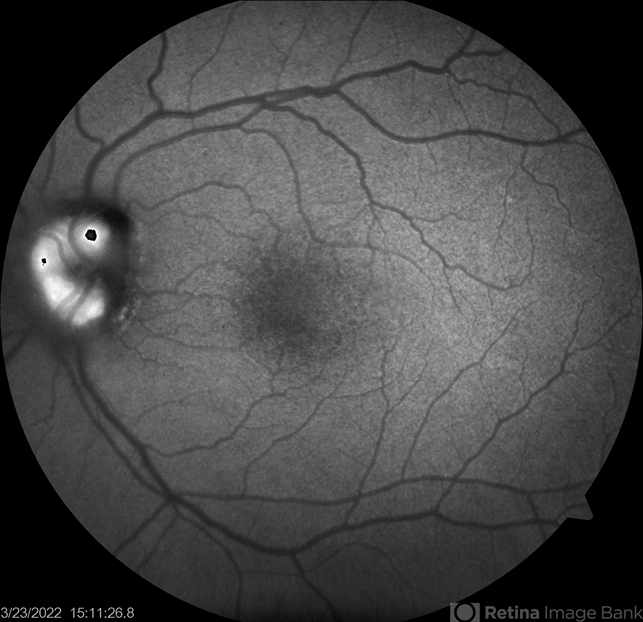

- optic disc drusen, papilledema

- Fundus autofluorescence of a 41-years old patient with combined true papilledema and optic nerve head drusen, treated with Diamox and monitored.